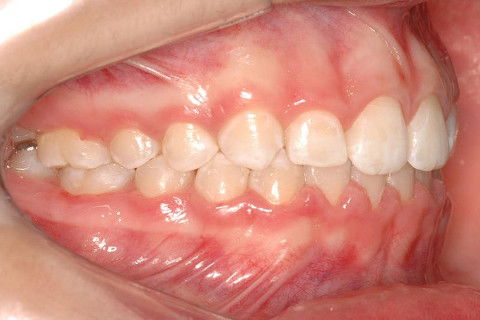

FINALIZAÇÃO; ELÁSTICO DE CLASSE II DUPLO.

FINALIZAÇÃO; ELÁSTICO DE CLASSE II SIMPLES.

APARELHO FIXO METÁLICO ROTH + ELÁSTICO DE CLASSE II.